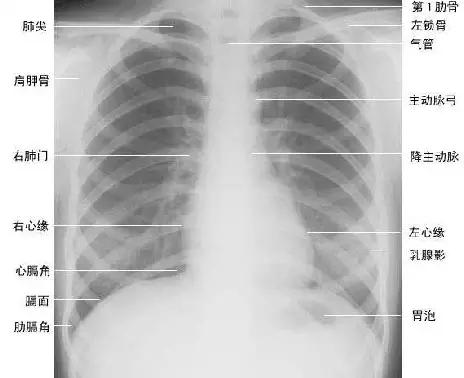

两肺含有空气,因而可与周围组织及器官形成鲜明的自然对比,胸部X线平片为诊断提供了极为有利的条件。由于胸部X线影像是胸腔内、外各种组织和器官重叠的复合影像,同时常常存在解剖变异等因素,因此掌握正常X线解剖是识别和分析胸部病变的基础。

下面为大家依次介绍胸部正常X线解剖

1、肺叶段X线解剖

肺叶

右肺:由水平裂和斜裂分为上、中、下三叶

左肺:由斜裂分为上、下两叶

斜裂:起自第5胸椎水平,倾斜向前下,大致与第6肋骨平行,止于前胸膜沟(前肋膈窦)后方数厘米的膈肌处。

水平裂:大致呈水平走形,与第4前肋大致同水平,前部常低于后部,外侧部常低于内侧部。

2、肺纹理

肺纹理为自肺门向肺野呈放射状分布的树枝状阴影,它主要是肺动脉的投影,肺静脉、支气管和淋巴管也参与形成。肺纹理由肺门向外围延伸,逐渐变细,至肺野外带渐细小而稀少,距侧胸壁内缘约1cm范围内的肺野基本无肺纹理可见(图下图)。

3、肺野、肺带的划分

纵隔两旁含气的肺在胸片上所显示的透明区域称肺野,其透明度随呼吸而改变,深吸气时肺内含气量增多,透明度增高,呼气时则相反。

为便于指明病变的部位,通常人为地将一侧肺野纵向分为三等分,即内、中、外带。又分别在两侧第2、4肋骨前端下缘划一水平线,将肺野横向分为上、中、下三个肺野。(如上图)。

7、胸廓

正常胸廓由软组织与骨骼组成,两侧对称。

① 骨性结构: 肋骨、锁骨、肩胛骨、胸椎

② 软组织结构:胸锁乳头肌、锁骨上皮肤皱褶、胸大肌、女性乳房 / 乳头